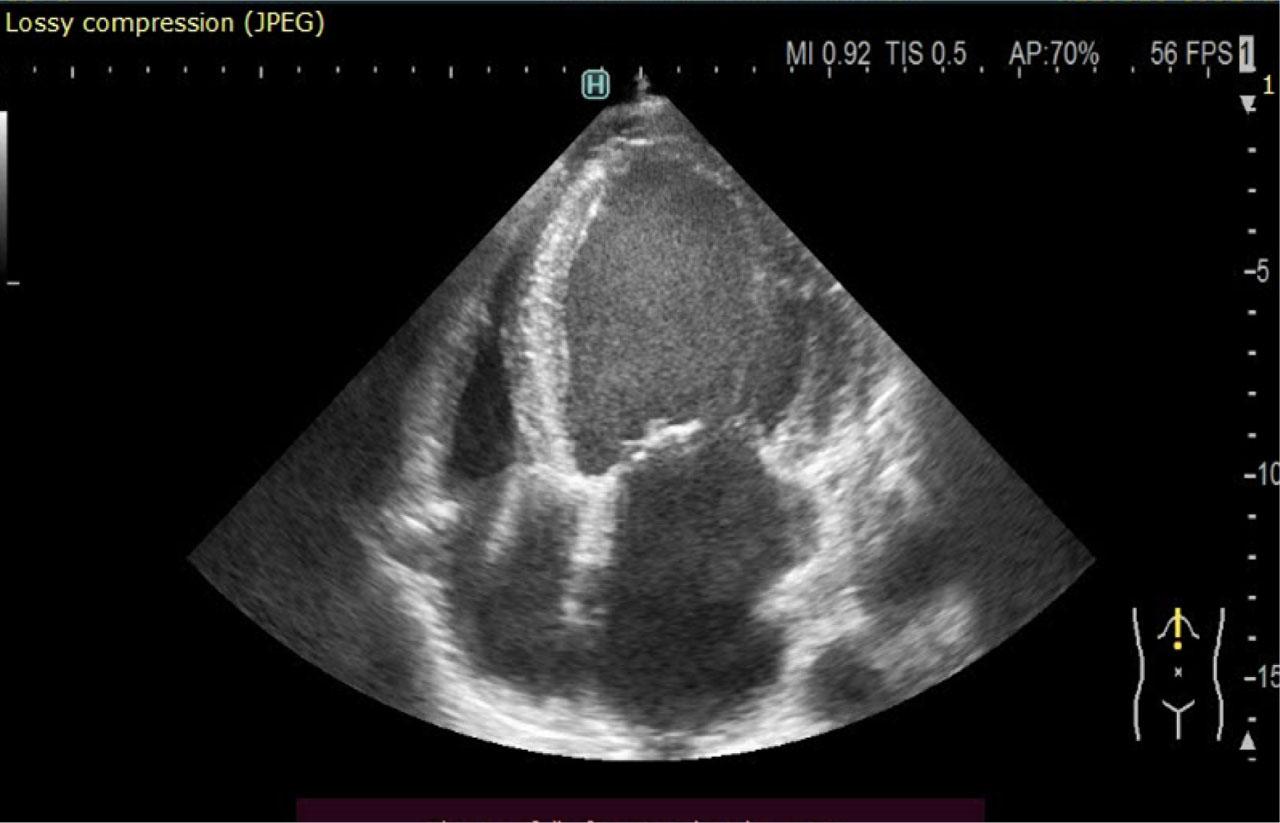

The electrocardiogram (ECG) at admission (Figure 2) reveals a sinus rhythm with a frequency of 65 beats/minute, with the presence of the q wave suggestive for necrosis in the inferior leads, followed by negative T waves in the same leads and ST segment depression of 1–2 mm in V4–V6. Transthoracic echocardiography revealed a dilated left ventricle with severe systolic dysfunction (LVEF = 30%), expressed as diffuse hypokinesia, more accentuated on the antero-lateral and inferior walls, the basal segments being akinetic (Figure 3).

Transthoracic echocardiography apical 4C view—dilated left ventricle with significantly impaired systolic function. ICD lead visible in the right chambers.